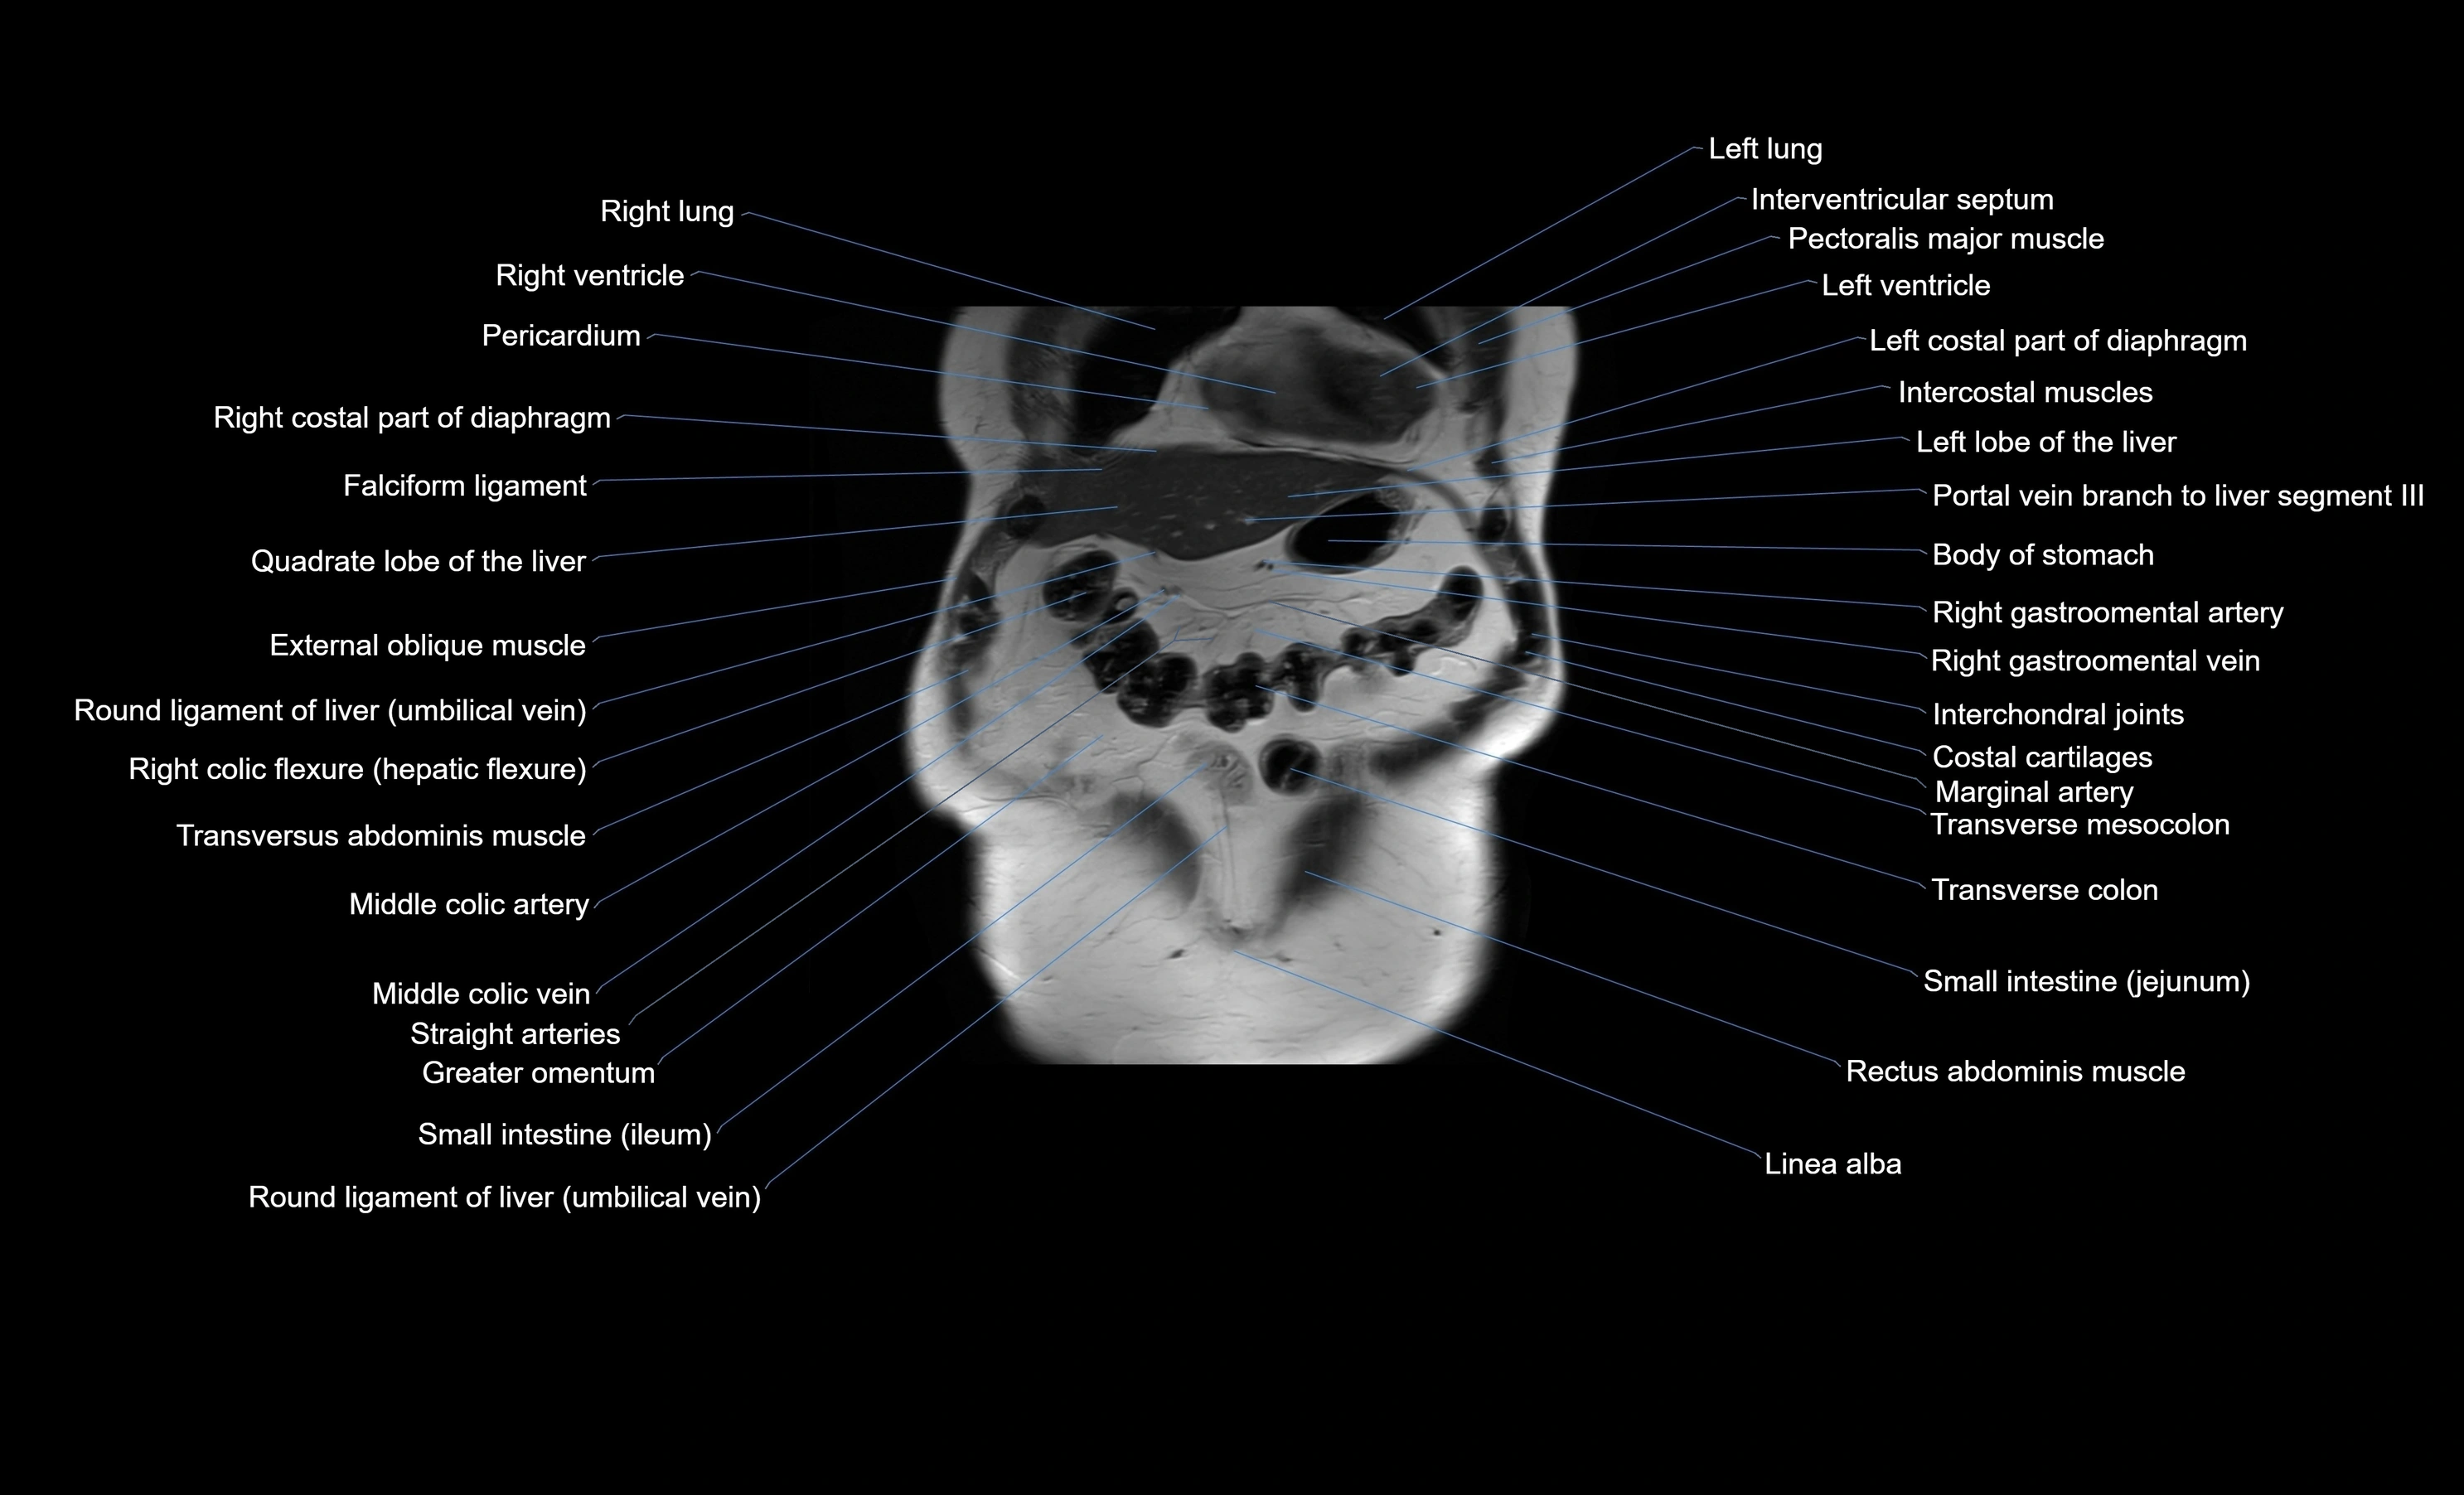

MRI images